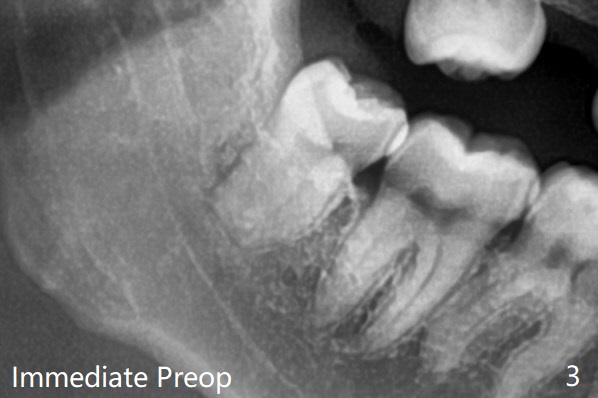

每个牙槽窝放置0.5cc骨水泥(Bone Cement (Bond Apatite from Augma)),覆盖半块胶原塞,4-0铬羊肠线缝合(图四)。